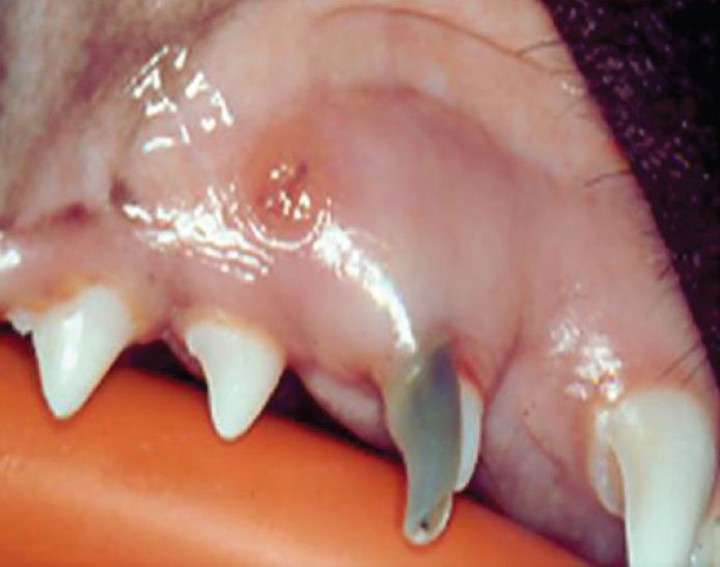

Fractura de diente deciduo

Debido a que los dientes de leche son más largos y finos que sus homólogos persistentes, se fracturan con más facilidad[ Hale FA. Juvenile Veterinary Dentistry. Vet Clin North Am: Small Anim Pract. 2005; (35):789-817. [PubMed] ] (Fig. 3). En la mayoría de las ocasiones, la etiología es traumática, y debido al gran tamaño de la cavidad pulpar, se produce una fractura complicada con exposición pulpar.[ Brook AN. Pathology in the pediatric patient. En: Niemiec B: Small Animal Dental, Oral and Maxillofacial Disease. Manson Publishing. London 2010; 90-123. , Ulbricht RD, Marretta SM, Klippert LS. Surgical extraction of a fractured nonvital deciduous teeth in a tiger. J Vet Dent 2003, 24(4): 209-212. ] Este tipo de fracturas son dolorosas,[ Cohen AS, Brown DC. Orofacial Dental pain emergences: endodontic diagnosis and management. En: Cohen AS and Burns RC: Pathways of the pulp. Ed. Mosby, St. Louis 2002; 31-76. , Golden AL, Stoller NS, Harvey CE. A survey of oral and dental diseases in dogs anesthetized at a veterinary hospital. J Amn Anim Hosp Assoc 1982; 18 : 891-899. ] y rápidamente originan pulpitis, infección y necrosis pulpar y abscesos periapicales, que pueden afectar a la corona de los dientes permanentes, dañándolos.

<p>Fractura coronal complicada del canino deciduo superior izquierdo (504). Nótese la exposición y necrosis de la pulpa, el cambio de coloración, y la aparición de una fístula en la zona apical.</p>

Fractura coronal complicada del canino deciduo superior izquierdo (504). Nótese la exposición y necrosis de la pulpa, el cambio de coloración, y la aparición de una fístula en la zona apical.

El tratamiento recomendado es la exodoncia de la pieza. Siempre es necesaria la realización de radiografías dentales previas a la extracción, que nos van a permitir conocer la morfología de la raíz, detectar posibles lesiones añadidas e identificar la ubicación del diente permanente.[ Brook AN. Pathology in the pediatric patient. En: Niemiec B: Small Animal Dental, Oral and Maxillofacial Disease. Manson Publishing. London 2010; 90-123. ]